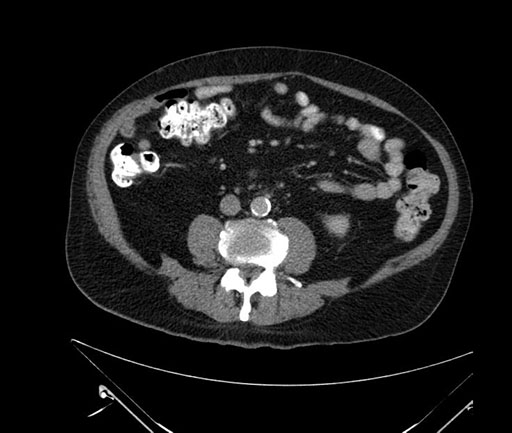

Axial - 3 months prior